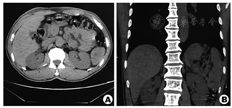

PSA缺乏特异临床表现,多数患者可出现腹部不适等一些非特异性表现。约10%表现出恶性肿瘤警示征:不明原因发热、乏力、体重减轻等,约30%因脾自发破裂就诊。实验室检查同样缺乏特异性,常有贫血、血小板减少,也可能观察到血小板增多、白细胞增多,血沉加快等。超声、CT、MRI等检查都可能发现脾脏的异常,但很难同脾脏的其他良性或恶性肿瘤鉴别。CT具有相对较高的诊断效能,在平扫时可以发现增大的脾脏,内有高密度或低密度结节,增强时结节不均匀强化,有时可以发现大量钙化点[4]。PET-CT在鉴别良恶性上有一定帮助,SUXmax>6需高度怀疑恶性肿瘤。此患者在术前未准确诊断,这也说明影像学在诊断PSA上存在较大局限性。此外,回顾患者入院前1年体检时的CT平扫,在脾脏下极已经能够发现可疑病灶(图3),但被CT诊断所忽视。所幸疾病未发生质变,这说明影像医生对于脾脏肿瘤的认识和重视还需提升。其最终的诊断需依赖病理学检查,但不推荐活检,因为存在出血及肿瘤破裂播散的风险。